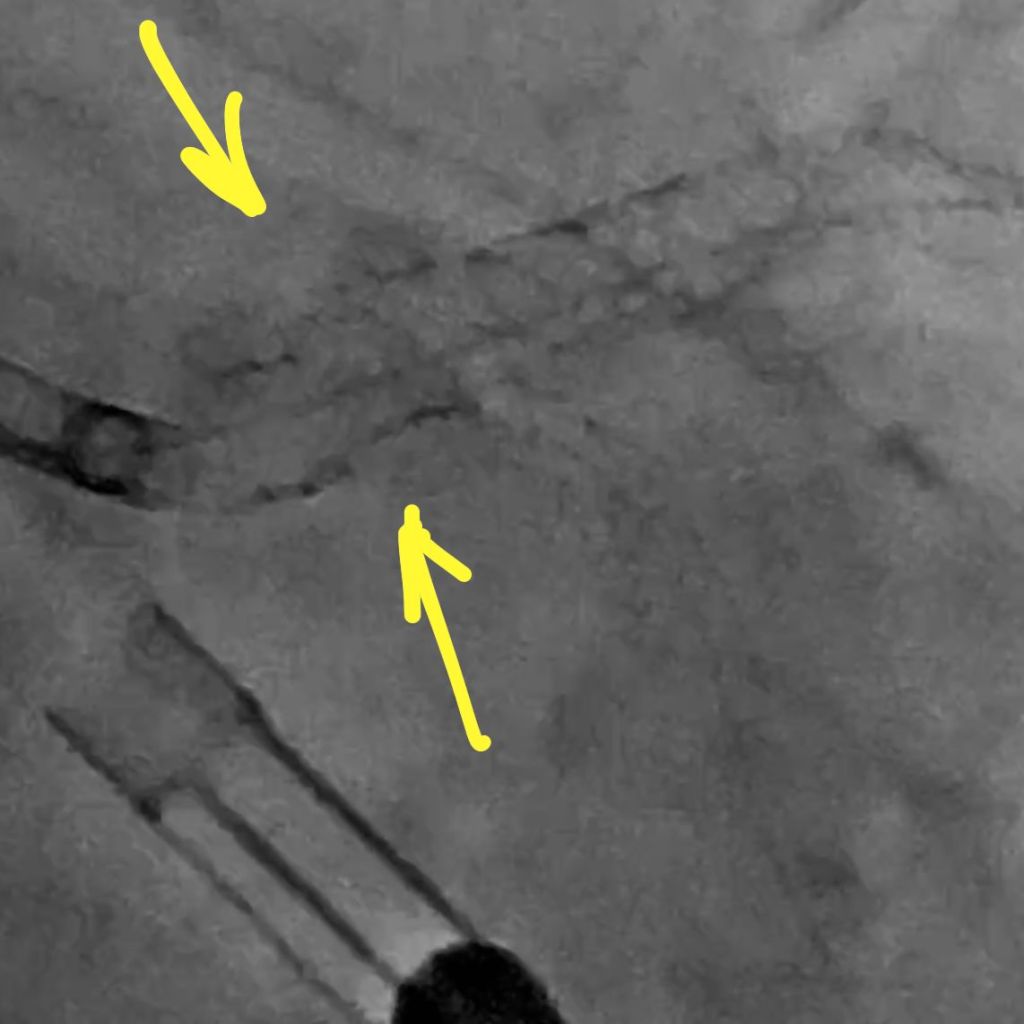

Also, the guide had softened and came out. Note the stent deformation on account of the calcium module at the ostium. There is a recoil after high-pressure NC ballooning.

We resolved that issue with a TurnPike LP microcatheter. You can drive the MC by torquing it. We knew we were going to fix the LAD with rota so I did a 1.5 mm angioplasty to allow the LAD to breathe while we did IVUS.